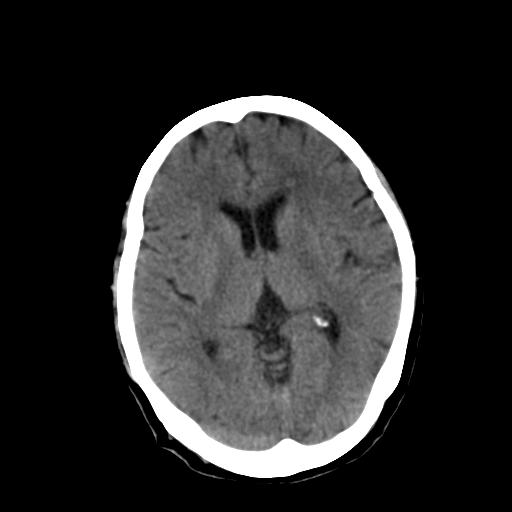

女,72岁,咳嗽一周余,突发右下肢无力二天。

pe:bp-140、80mmhg,精神可,伸舌居中,右上肢肌力正常,右下肢肌力0级,巴氏征+

来院做头颅+胸部ct平扫

这个病人首先是胸部病变的定位到底是肺内还是肺外。仔细观察块影位于胸膜下,与胸膜间有透亮带,且近端血管未见明显推移而是引流样改变,形态分叶,说明这个病灶位于肺内胸膜下。很可能是腺癌,腺癌最易致颅内高密度转移灶。局部胸膜有侵犯。

本例颅内见多发大小不等高密度灶,有强化及水肿;另外,胸锁关节层面可能是第四胸椎及右侧肋骨起始部骨质欠连续,椎旁软组织肿胀,建议调骨窗观察。

诊断:右下肺癌伴颅内、胸椎、肋骨转移可能性最大。

右侧胸膜间皮瘤,双肺大泡,颅内多发转移(右顶叶、左侧侧脑室前角放射冠区)并出血。

左侧额叶及右顶叶实质内病灶首先应该考虑是转移性肿瘤伴出血{结合胸部强化}.